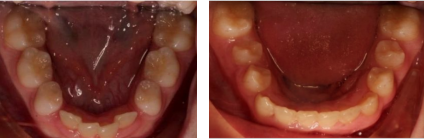

早期隐形矫治器使用适合青少年口腔的独特附件、替牙期萌出帽等,精确设计和引导牙齿萌出、移动,控制牙弓长度、宽度,阻断畸形发展,引导牙、颌、面整体正常发育。

1、牙弓发育问题→可预测扩弓,尤其是传统矫治器难以完成的下颌扩弓